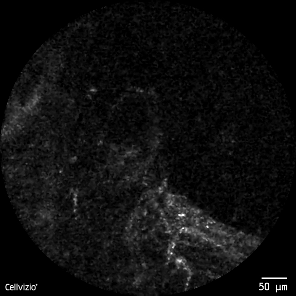

图1 版权图片 不授权转载